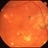

- chorioretinitis, tularemia sepsis, disseminated chorioretinitis

- Old chorioretinal scars following Tularemia infection in the right eye of a 60ish-year-old white male. He was squirrel hunting as a young man, and shot a squirrel but did not kill it. When he picked it up, it bit him, from which he contracted tularemia sepsis.